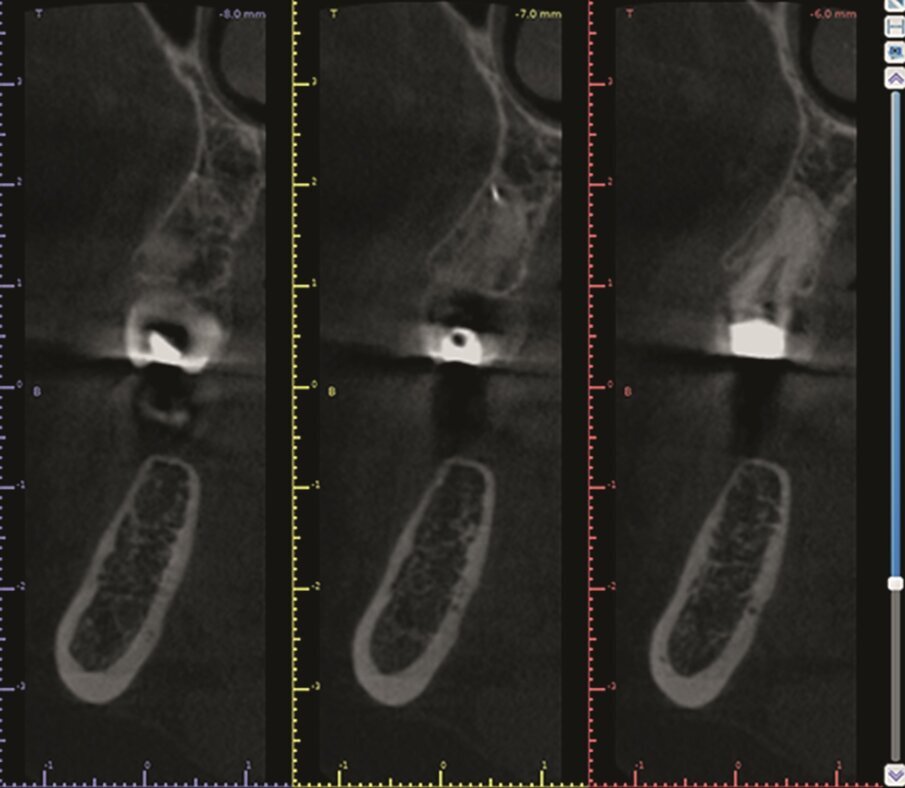

Fig. 1a–d: Pre-op CBCT scan of tooth #36. The axial (a), …

…and sagittal views (c) showed a hypo-dense zone around the apical third of the mesial and distal roots and intact cortical buccal bone.

A template that marked the limits of a cortical window to accurately reach the apical area of both roots was designed (d).

A 63 year old female patient, with a non-contributory medical history, consulted owing to moderate pain associated with her previously treated mandibular left first molar. CBCT revealed that a mesiobuccal canal had being missed during initial treatment, that the mesial and distal roots were affected by an apical lesion, and that the cortical buccal bone was intact.

Retreatment was done in two appointments, and calcium hydroxide was used as the intra-canal dressing after removing the previous filling material and cleaning and shaping three canals. After one week, root canal therapy was completed. Two months later, symptoms persisted and clinical examination revealed pain on vertical percussion; periodontal probing depth and mobility were within normal limits. CBCT revealed no signs of bone healing (Figs. 1a–c). The diagnosis for tooth #36 was previously treated symptomatic periapical periodontitis, and the treatment of choice was guided EMS.

An intra-oral scan (TRIOS, 3Shape) of the mandible, and the resulting STL file was combined with the DICOM files of the CBCT scan to plan a surgical guide using the Blue Sky Bio software. A template that marked the limits of a cortical window to accurately reach the apical area was designed and printed (Fig. 1d).